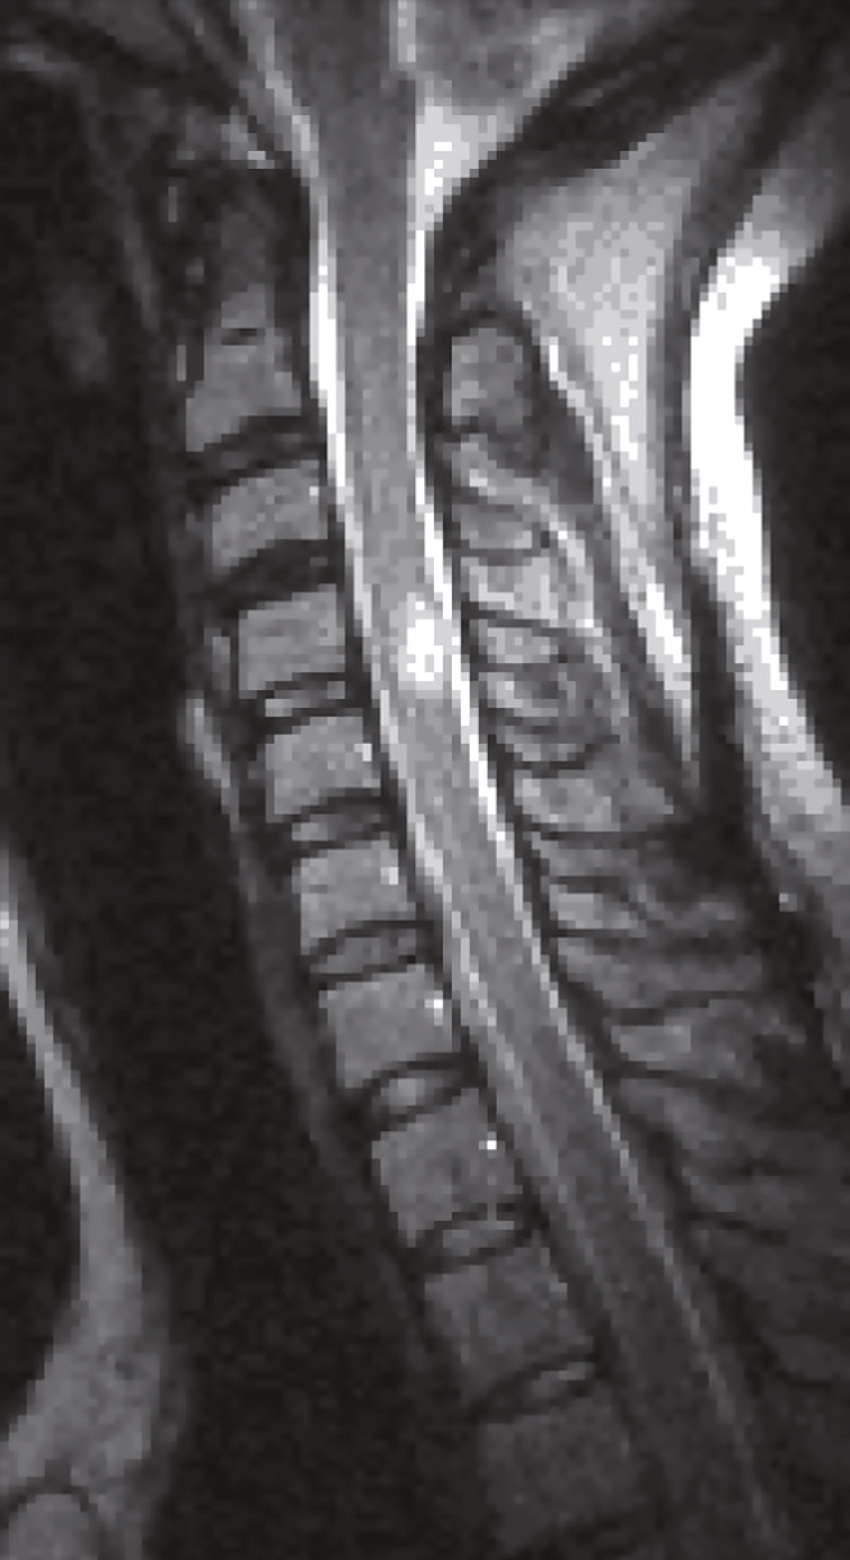

Une IRM médullaire cervicale est réalisée (fig. 31.6). Quelle(s) est (sont) l’(les) affirmation(s) exacte(s) correspondant à cette planche d’IRM ?

- A 584hypersignal extramédullaire à hauteur de C4-C5

- B hypersignal extramédullaire à hauteur de C3-C4

- C hypersignal intramédullaire à hauteur de C3-C4

- D hypersignal intramédullaire à hauteur de C4-C5

- E hypersignal intramédullaire à hauteur de C5-C6